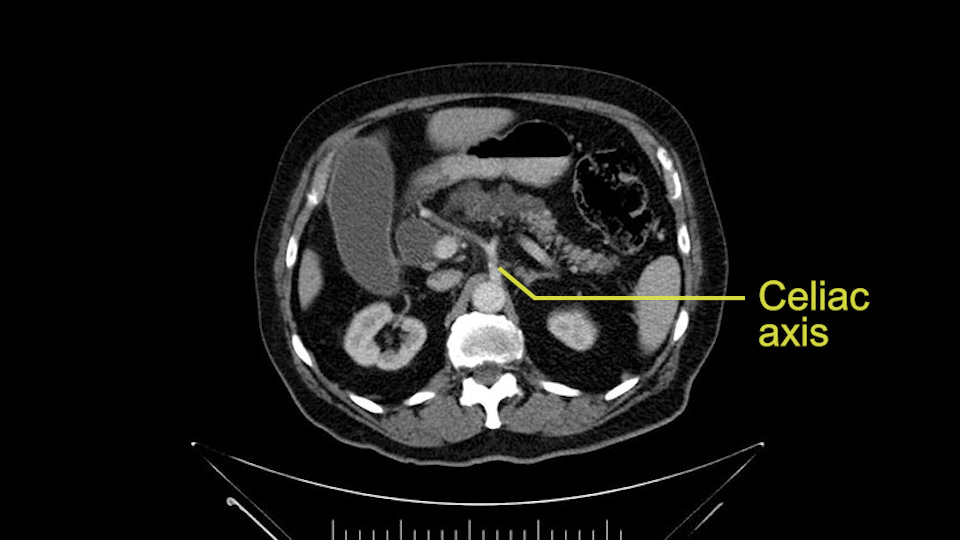

Then you look for anomalies. The one you worry about the most doing a Whipple is a replaced or aberrant right hepatic artery coming off the SMA at its origin. So again, find the SMA. You can find it because the renal vein goes through it. Follow it up, up-up-up. Nothing coming off of there that I can see here. Nothing coming off of it, nothing coming off of it and just to confirm it, look at the celiac trfurcation. There’s the celiac, there’s the bifurcation, there's the splenic artery, hepatic artery. Make sure there’s a right, which there is here. The right usually goes under the bile duct: important when you’re going around the bile duct to do a Whipple. A replaced right goes under the portal vein and the bile duct way over here on the right. That’s about it.

To plan a pancreatoduodenectomy, we start by reviewing the vascular anatomy, especially the origin of the celiac trunk, here, in front of the aorta, looking for any evidence of stenosis. In addition, we look at the origin of the superior mesenteric artery, to look for any branches, and any replaced right hepatic arteries coming from the superior mesenteric artery; which does occur in about 12% of the population.

First, the stenosis of the celiac trunk, which can be caused by arteriosclerosis, especially in a patient who is 83, or in patients who have arcuate ligament; we do see it, sometimes in much younger patients. In those cases, it may be that the circulation of the hepatic artery comes entirely from the gastroduodenal artery and its anastomoses, through the pancreaticoduodenal arteries, coming from the superior mesenteric artery. This means that before the gastroduodenal artery is ligated, we first clamp and wait 30 seconds to a minute, to feel and check the arterial inflow to the liver. If the pulse is diminished or there is a complete absence of the pulse, the surgery should be modified or probably a pancreatoduodenectomy cannot be done, because of the risk - when ligating the gastroduodenal artery - of causing fulminant hepatic ischemia postoperatively.

Para planear una pancreatoduodenectomía, se debe revisar la anatomía vascular, especialmente el origen del tronco celíaco, aquí, por delante de la aorta, buscando areas de estenosis y por otro lado, el origen de la arteria mesentérica superior, para evaluar -sobre todo- si hay ramas, arterias hepáticas derechas provenientes de la mesentérica superior; lo cual ocurre en alrededor del 12% de la población.

La primera que mencionamos, la estenosis del tronco celíaco, que puede ser causada por arterioesclerosis, especialmente en este paciente de 83 años, ó por pacientes que tienen ligamento arcuato; ese sí lo vemos, a veces, en pacientes mucho más jóvenes. En esos casos, puede resultar que la circulación de la arteria hepática provenga completamente a través de la arteria gastroduodenal y sus anastomosis, por las arterias pancreaticoduodenales, provenientes de la mesentérica superior.